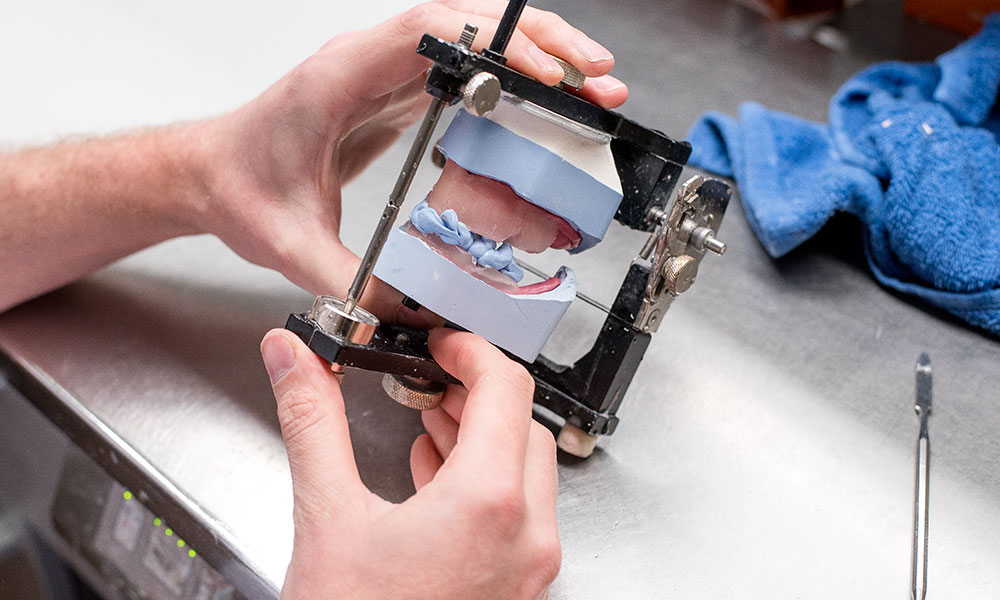

KUNSTGEBITTEN, KLIKGEBITTEN, REPARATIES EN ADVIES

Gun uzelf een gebit om in te lijsten en een lach die gezien mag worden. Als erkend tandprothetici zijn wij specialist in het aanmeten van een kunstgebit, klikgebit op implantaten of een gedeeltelijke prothese. U kunt zonder verwijzing bij ons terecht omdat wij zelfstandig zorgverlener zijn.

WAARVOOR KUNT U BIJ DE TANDPROTHETICUS TERECHT?

- reparatie en aanpassing van het kunstgebit

- vernieuwing van een kunstgebit

- kunstgebit op implantaten, klikgebit